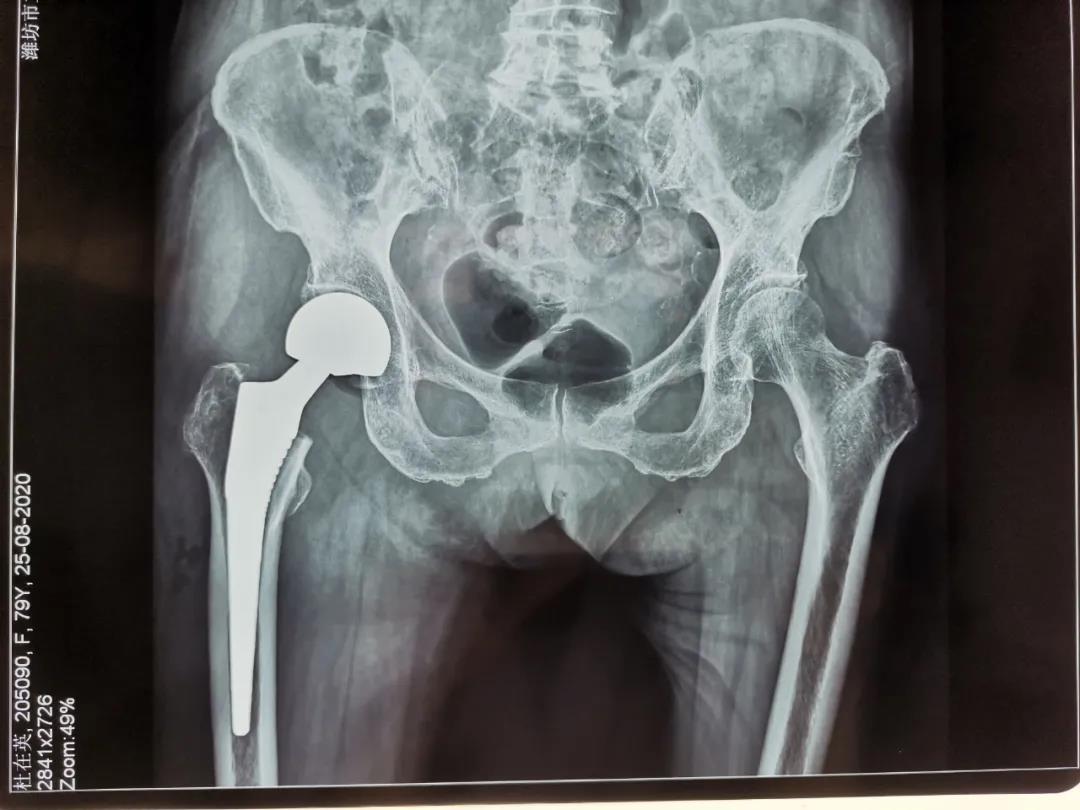

人工股骨頭置換手術(shù)治療老年股骨頸骨折

79歲的杜大娘在家不慎摔倒,跌傷右髖部,許冬雷主任為其主刀行右股骨頸骨折人工股骨頭置換術(shù),用時(shí)短,出血少,患者清醒后就說(shuō)腿不疼了,術(shù)后第一天見(jiàn)到醫(yī)生就豎大拇指,激動(dòng)地說(shuō):“手術(shù)前我很害怕、也很焦慮,沒(méi)想到手術(shù)后一點(diǎn)也沒(méi)有感覺(jué)到疼痛”。術(shù)后第3天就可以下地活動(dòng)了,老人的生活又恢復(fù)了往日的悠然自在。

骨二科采用人工半髖關(guān)節(jié)置換(高齡身體基礎(chǔ)差患者)或人工全髖關(guān)節(jié)置換(相對(duì)年輕,身體條件較好患者)能夠迅速恢復(fù)患者的下床行走及生活自理能力,避免長(zhǎng)期臥床引起的并發(fā)癥,減輕患者家屬的護(hù)理負(fù)擔(dān),提高患者的生活質(zhì)量,是治療老年股骨頸骨折首選治療方案。